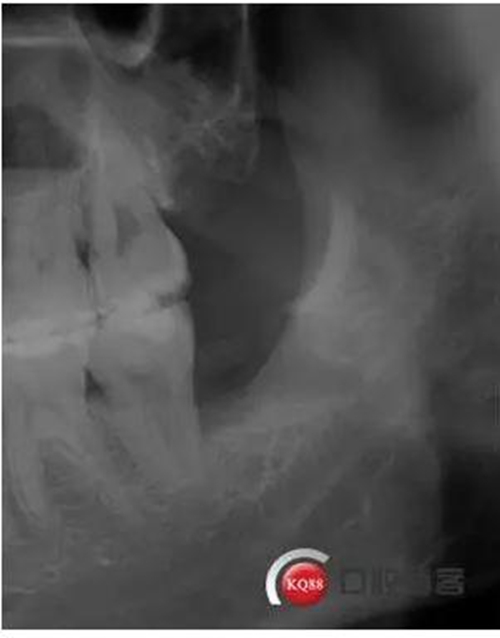

檢查:口內(nèi)可見38未完全萌出,無松動,周圍牙齦顏色正常,叩診(—)觸診(—),X線顯示近中阻生,雙根

處理:治療計(jì)劃及費(fèi)用已說明,知情同意后,排除拔牙禁忌癥:口腔黏膜消毒,左下頜阻滯麻醉成功后,切開翻瓣,渦輪機(jī)去除近中阻力,向近中挺出患牙,拼對牙體完整,清創(chuàng),置明膠海綿,縫合傷口,咬棉球壓迫止血